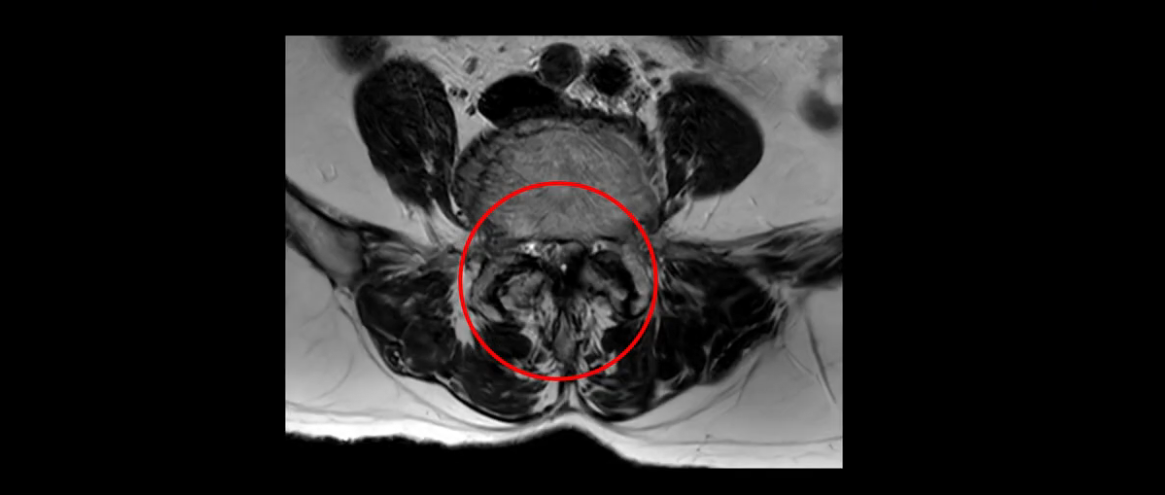

먼저 이분 MRI를 보고 자세히 설명해 드린 후 어떻게 허리 여러 마디에서 협착과 전방전위로 신경이 심하게 눌려 보이는 환자가 수술 없이 좋아질 수 있는지, 또 치료는 어떻게 하는지 설명해 드리겠습니다.

또 척추관협착도 매우 심합니다.

척추관이 심하게 좁아져 있습니다.

이렇게 여러 마디가 안 좋고 뼈도 밀려 나가 있으니까 나사박는 수술해야 하는데, 대학병원에서도 수술을 한 번에 못 하고 두 번에 나눠서 해야 한다고 들으셨습니다. 왼쪽으로 신경가지가 빠져나가는 추간공도 많이 좁아져 있습니다.

이렇게 신경 구멍들이 좁아져 있고 신경이 눌리니까 엉덩이와 다리가 너무 저리고 아파서 아예 일어서질 못하니까 휠체어를 타고 병원에 내원하셨는데요. 그럼 어떻게 이분처럼 신경이 눌려있는 환자분들을 수술 없이 치료해서 잘 걷게 만들고 엉덩이와 다리가 저리고 아픈 증상이 사라지게 할까요? 지금부터 설명해 드립니다.